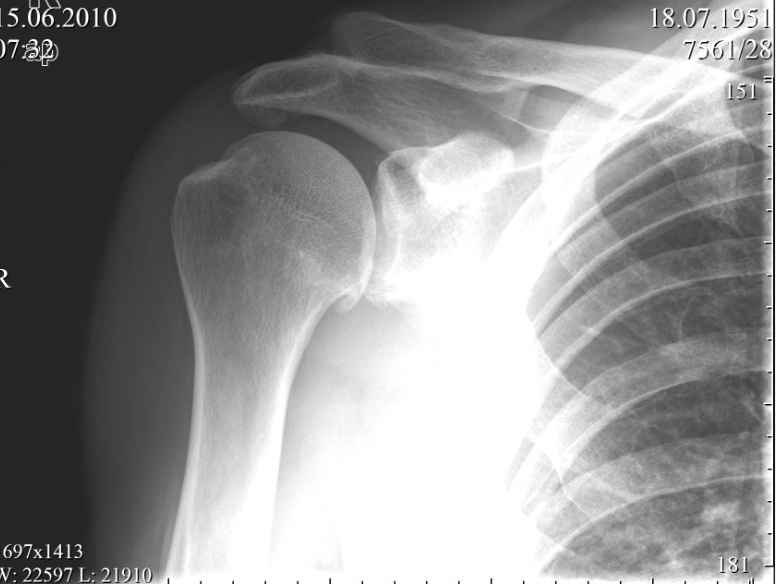

Акромиально - ключичное сочленение -застарелый разрыв |

Пациент, мужчина, 59 лет обратился в июне с жалобами на умеренные периодические боли и хруст в области правого плечевого сустава.

В анамнезе - 1,5 года назад упал, ударился задней поверхностью локтевого сустава, при отведенной правой руки в плечевом суставе и согнутом в локтевом. Обратился за мед. помощью, по месту жительства, сказали, что ничего страшного, повесили травмированную конечность на косынку.

Но при движении правой рукой стоит ТАКОЙ хруст, что слышен на расстоянии. Пальпаторно, при движении правой рукой,ощущается подвижность в акромиально-ключичном сочленении, и боли при отведении в правом плече более 120 градусов.

Я подумывая об операции, но побаиваюсь за результат. Нужно иссечь рубцы, низвести акромиальный конец ключицы (а она будет "пружинить")и фиксировать крючковидной пластиной к акромиону, не исключается выполнение акромионопластики. Удержит ли пластина и удержатся ли взаимоотношения в акромиально-ключичном сочленении, после удаления пластины?

Тут вспомнился разговор с профессором Джолдасом Кулджановым, о необходимости восстановления клювовидно-ключичной связки. Хотелось бы освежить этот разговор в своей памяти и попросить профессора найти время и рассказать еще раз о целесообразности и технике восстановления клювовидно-ключичной связки, ну выслушать мнение коллег по Ортофоруму.